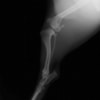

術前左後肢側面像

術後左後肢側面像

手術前後のTPA(脛骨高平部の角度)を測定しています。

約29°から約10°へ矯正されています。

本症例は、走った後に左後肢を挙上していることを主訴に来院されました。触診時に左膝関節のクリック音を聴取、レントゲン検査にて左脛骨の前方変位が認められました。術中に、前十字靱帯の断裂及び内側半月板の損傷、内側の軟部組織の顕著な腫脹を確認。半月板切除、TPLOを実施しました。周囲組織への炎症の波及もあったため回復に時間を要しておりますが、徐々に跛行頻度は減少傾向にあり、現在も経過観察中です。術前に約29°あったTPAは術後に約10°まで矯正されました。